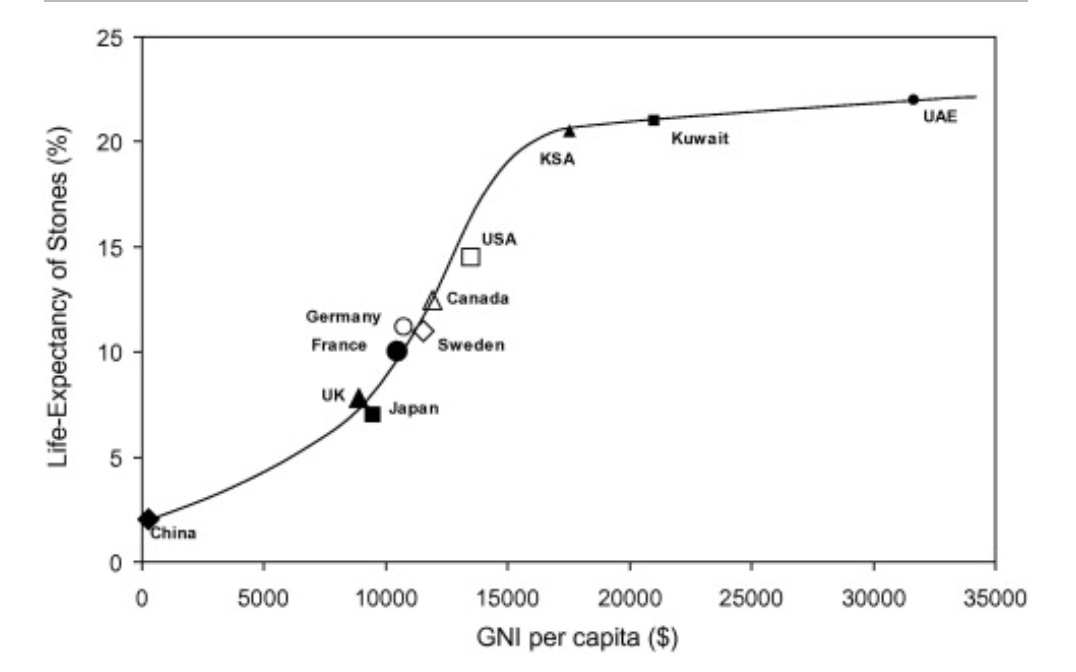

⛔اسباب تكوين الحصوات وليه أحنا من اكثر الدول الي تعاني من الحصوات.

⛔اسباب تكوين الحصوات وليه أحنا من اكثر الدول الي تعاني من الحصوات.